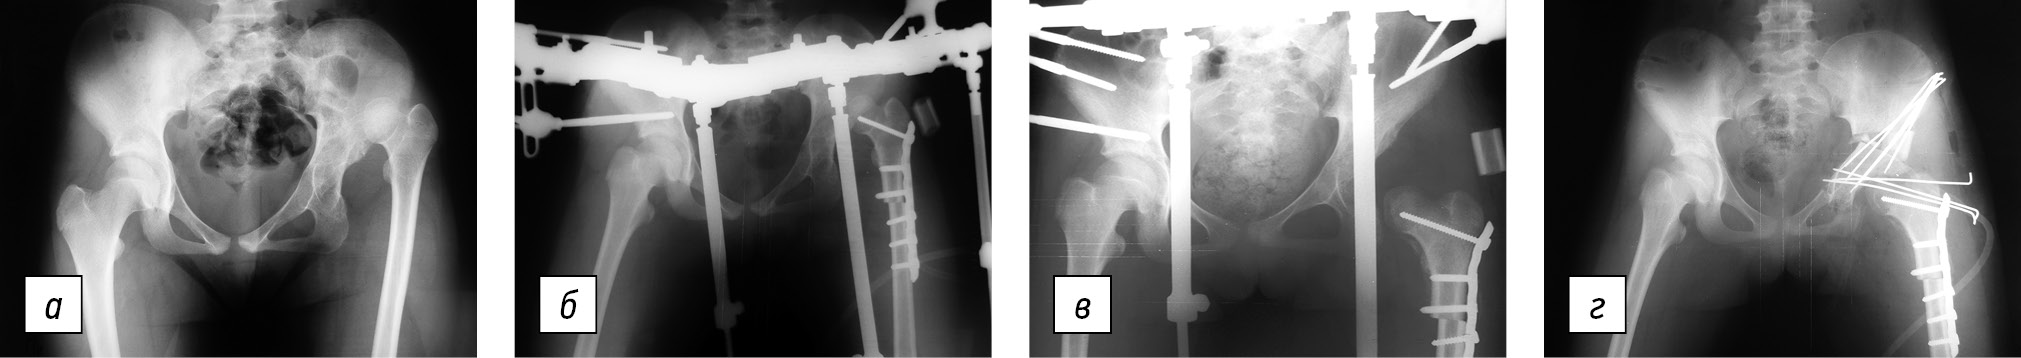

Всем пациентам проведено хирургическое лечение, которое состояло из двух этапов: на первом этапе выполняли рациональную укорачивающую деторсионно-варизирующую остеотомию бедренной кости с наложением дистракционного аппарата, с помощью которого в послеоперационном периоде устраняли остаточное смещение головки бедренной кости. На втором этапе при противопоставлении головки бедренной кости вертлужной впадине осуществляли открытое вправление и остеотомию таза с коррекцией вертлужной впадины (рис. 1).

Рис. 1. Рентгенограммы пациента Т., 13 лет, с высоким врожденным вывихом левого бедра: а — до лечения — подвздошный вывих, головка левой бедренной кости располагается на уровне крыла подвздошной кости, прерывистость линии Шентона — 6 см, ацетабулярный индекс — 60°, угол вертикального наклона впадины — 68°, шеечно-диафизарный угол — 125°, антеверсия шейки бедра — 50°; б — первый этап оперативного лечения — укорачивающая деторсионная остеотомия бедренной кости с наложением дистракционного аппарата на таз и левое бедро; резецированный костный фрагмент (2,5 см) располагается в подкожной клетчатке в ацетабулярной зоне; в — рентгенограмма через 2 нед. после начала дистракции — головка левой бедренной кости низведена до уровня нижнего края вертлужной впадины; г — второй этап оперативного лечения — дистракционный аппарат демонтирован, выполнены открытое вправление головки бедренной кости в вертлужную впадину, тройная остеотомия таза слева с транспозицией вертлужной впадины